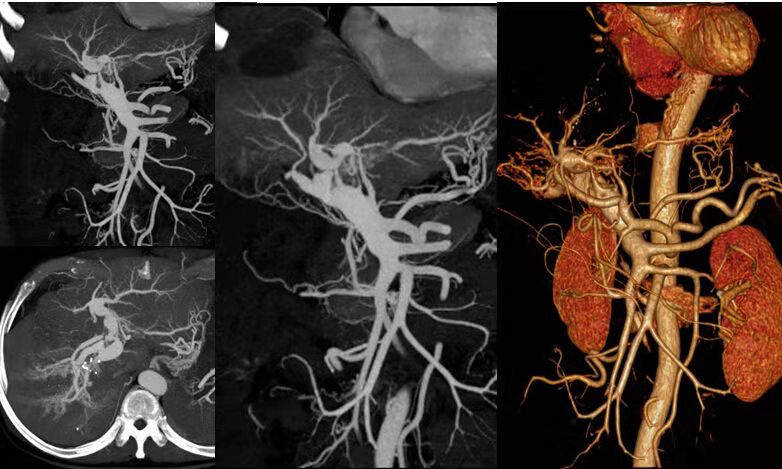

除開展全身(shēn)各部位常規檢查外,還先後開展了(le)全身(shēn)血管CTA成像、骨關(guān)節CT三維重建、磁共振擴散加權成像DWI、灌注成像PWI、磁敏感成像SWI、胰膽管水成像MRCP、泌尿系水成像MRU、内聽(tīng)道水成像、外周血管介入診療、消化(huà)道支架成形術、椎體(tǐ)成形術、椎間(jiān)盤消融術、經皮穿刺活檢術等新(xīn)技術。

腸系膜動脈CTA

頭頸部血管CTA